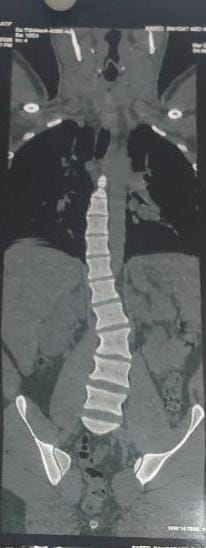

وأضاف مدكور أنه جرى استقبال المريض وهو يعانى من الالام شديدة بالظهر مع عدم الاستجابه للعلاج الدوائي والعلاج الطبيعى وعقب الفحص تبين وجود اعوجاج بالفقرات الصدريه والقطنيه بالعمود الفقري.

فيما أوضح الدكتور احمد البيلى وكيل المديرية للطب العلاجى أنه عقب مناظرة الاشعة والفحوصات تم إجراء العملية التى استغرقت 4 ساعات كاملة لإصلاح الاعوجاج بواسطه تثبيت الفقرات الصدريه والقطنيه واستعدال العمود الفقرى مع خروج المريض من المستشفى وتحسن حالته.